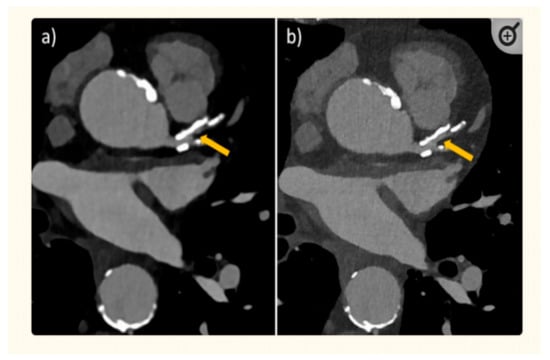

- Allmendinger, T.; Nowak, T.; Flohr, T.; Klotz, E.; Hagenauer, J.; Alkadhi, H.; Schmidt, B. Photon-Counting Detector CT-Based Vascular Calcium Removal Algorithm: Assessment Using a Cardiac Motion Phantom. Investig. Radiol. 2022, 57, 399–405. [Google Scholar] [CrossRef] [PubMed]

- Boccalini, S.; Si-Mohamed, S.A.; Lacombe, H.; Diaw, A.; Varasteh, M.; Rodesch, P.A.; Villien, M.; Sigovan, M.; Dessouky, R.; Coulon, P.; et al. First in-Human Results of Computed Tomography Angiography for Coronary Stent Assessment with a Spectral Photon Counting Computed Tomography. Investig. Radiol. 2022, 57, 212–221. [Google Scholar] [CrossRef] [PubMed]